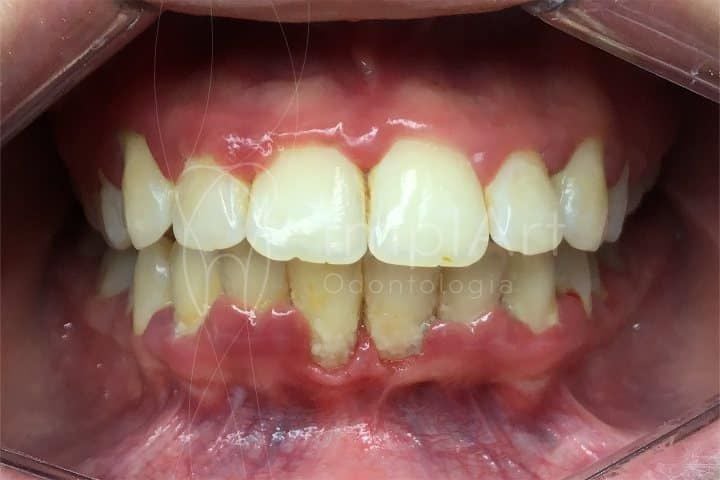

Vamos falar de gengivite. Sabe quando a gengiva fica inchada, vermelha e sangra fácil? Isso é um sinal de alerta que você não pode ignorar. Se não tratada, ela pode piorar e afetar a estrutura que segura seus dentes. Eu vejo muita gente negligenciando isso, mas é fundamental cuidar bem da sua boca.

Fica tranquila, vamos entender direitinho o que é essa tal gengivite expulsiva. Muita gente ouve falar e já se assusta, né? Mas a verdade é que ela tem uma causa bem clara e que a gente pode controlar. Basicamente, quando a gente negligencia a higiene bucal, as bactérias se acumulam e criam uma placa bacteriana. Essa placa, se não for removida, irrita a gengiva. Com o tempo, essa irritação pode levar a um processo inflamatório mais sério, que é a gengivite. A “expulsiva” no nome vem justamente do fato de que o corpo tenta “expulsar” essa inflamação e as bactérias que a causam, causando o inchaço e, às vezes, sangramento.

Pois é, a raiz do problema é quase sempre a mesma: o acúmulo de placa bacteriana e tártaro. A escovação e o uso do fio dental diários são os seus maiores aliados aqui. Sem eles, as bactérias se proliferam e liberam toxinas que irritam o tecido gengival. Essa inflamação faz a gengiva ficar mais sensível, avermelhada e, em alguns casos, ela pode até se retrair um pouco, como se quisesse se afastar daquela agressão. É o corpo dando um sinal de alerta!

Quando a gengivite se agrava, ela pode causar o que chamamos de “gengivite expulsiva”. Isso significa que a gengiva começa a se afastar dos dentes, criando espaços onde sujeira e bactérias se acumulam ainda mais. Imagina só, os dentes parecem mais longos e até a sensibilidade pode aumentar. É um sinal claro de que a saúde bucal precisa de atenção urgente.